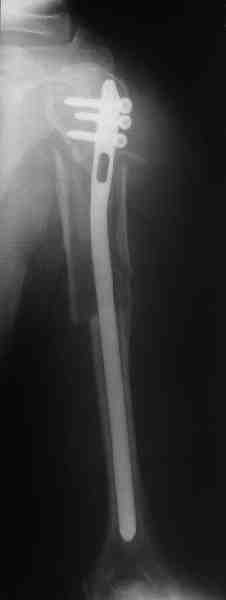

Прооперировали больную с переломом плеча все же гвоздем, Фото в приложении.

Отправитель: Никита Заднепровский 20 Август 2006, 22:38

Интересно, а канал рассверливали?

Гвоздик похоже ЦИТОвский?

Полагаю, бабушку можно поздравить с обретением

независимости. Судя по снимкам, неврологических расстройств нет и такая пациентка выпишется после снятия швов.

Немножко уточню ответы Максима.

Только сформировали канал в головке. Диафиз не рассверливали. Хотя при необходимости, конечно, рассверлили бы.

НЗ> Гвоздик похоже ЦИТОвский?

Гвоздь большеберцовый нашей модификации, действительно, их делает предпричятие "ЦИТО". Тут взят 9 мм, укорочен до 240 мм, сделано дополнительное отверстие самое проксимальное, ну и для дистального винта.

НЗ> независимости. Судя по снимкам, неврологических расстройств

НЗ> нет и такая пациентка выпишется после снятия швов.

Неврологии нет, а выписать можно хоть на второй день, швы можно снять и в местной больнице.

НЗ> Какие рекомендации Вы дадите этой женщине на ближайшие 6 месяцев?

Почему так надолго? На ближэайшие недели - разработка движений, и все. Полагаю, что недель после 4 никаких рекомендаций не будет нужно, просто жить обычной жизнью сельской пенсионерки.